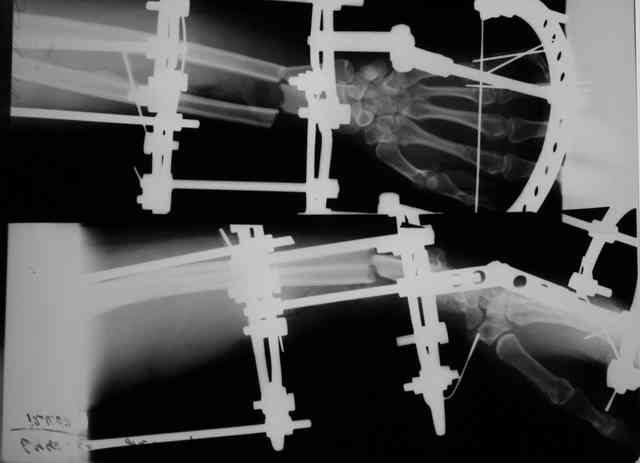

Травма 24 Октября этого года. Диагноз: Неполный травматический отрыв

нижней трети предплечья. Выполнено: ПХО открытого перелома, фасциотомия,

ЧКДО, шов лучевой артерии.

Размозженные мышцы-сгибатели кисти и пальцев экономно иссечены - не

сшивались.

Спустя месяц выполнена резекция 2,5 см некротизированного конца

проксимального отломка лучевой кости. На сегодняшний день по ладонной

поверхности предплечья с переходом на наружний край имеется рана с

дефектом мягких тканей, выполненная грануляциями с дна и с краев.